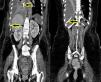

Mujer de 46 años, que ingresó en la UCI por hemorragia subaracnoidea. Como parte del tratamiento habitual, se decidió iniciar tratamiento con nutrición enteral (NE) por sonda nasogástrica (SNG). Se insertó la SNG según refieren sin incidencias. Se realizó Rx de tórax de control y se trasladó la enferma a radiología para realizar una TC toraco-abdominal programada. Al valorar los estudios se apreció en la Rx de tórax el extremo distal de la SNG en cavidad pleural derecha (fig. 1, flecha) que se confirmó con las imágenes de la TC como hallazgo incidental (fig. 2, flechas). Es importante resaltar la necesidad de realizar, antes de iniciar la NE, una Rx de tórax o un control ecográfico, para comprobar la localización del extremo distal en todo paciente al que se le coloca una SNG para nutrición. El no hacerlo puede producir serias complicaciones mecánicas.